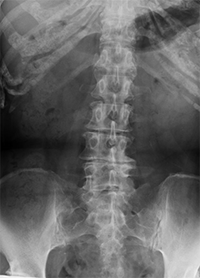

CT(Computed Tomography:コンピュータ断層診断装置)とは、放射線(X線)を利用して人の体内を撮影し、断面像として描き出す検査です。

短時間で広い範囲を撮像することができるため、救急医療の現場をはじめとして、非常に良く用いられている検査です。

また、解像度が高く細かい画像が得られるので、小さながんの転移などを見つけるのが得意です。

そのほか、体の広い範囲を一度に確認したい場合(がんの転移の検索など)や骨の情報が必要な場合(骨折、骨転移など)、肺の病気の診断・経過観察などを目的とする場合もCT検査が必要です。